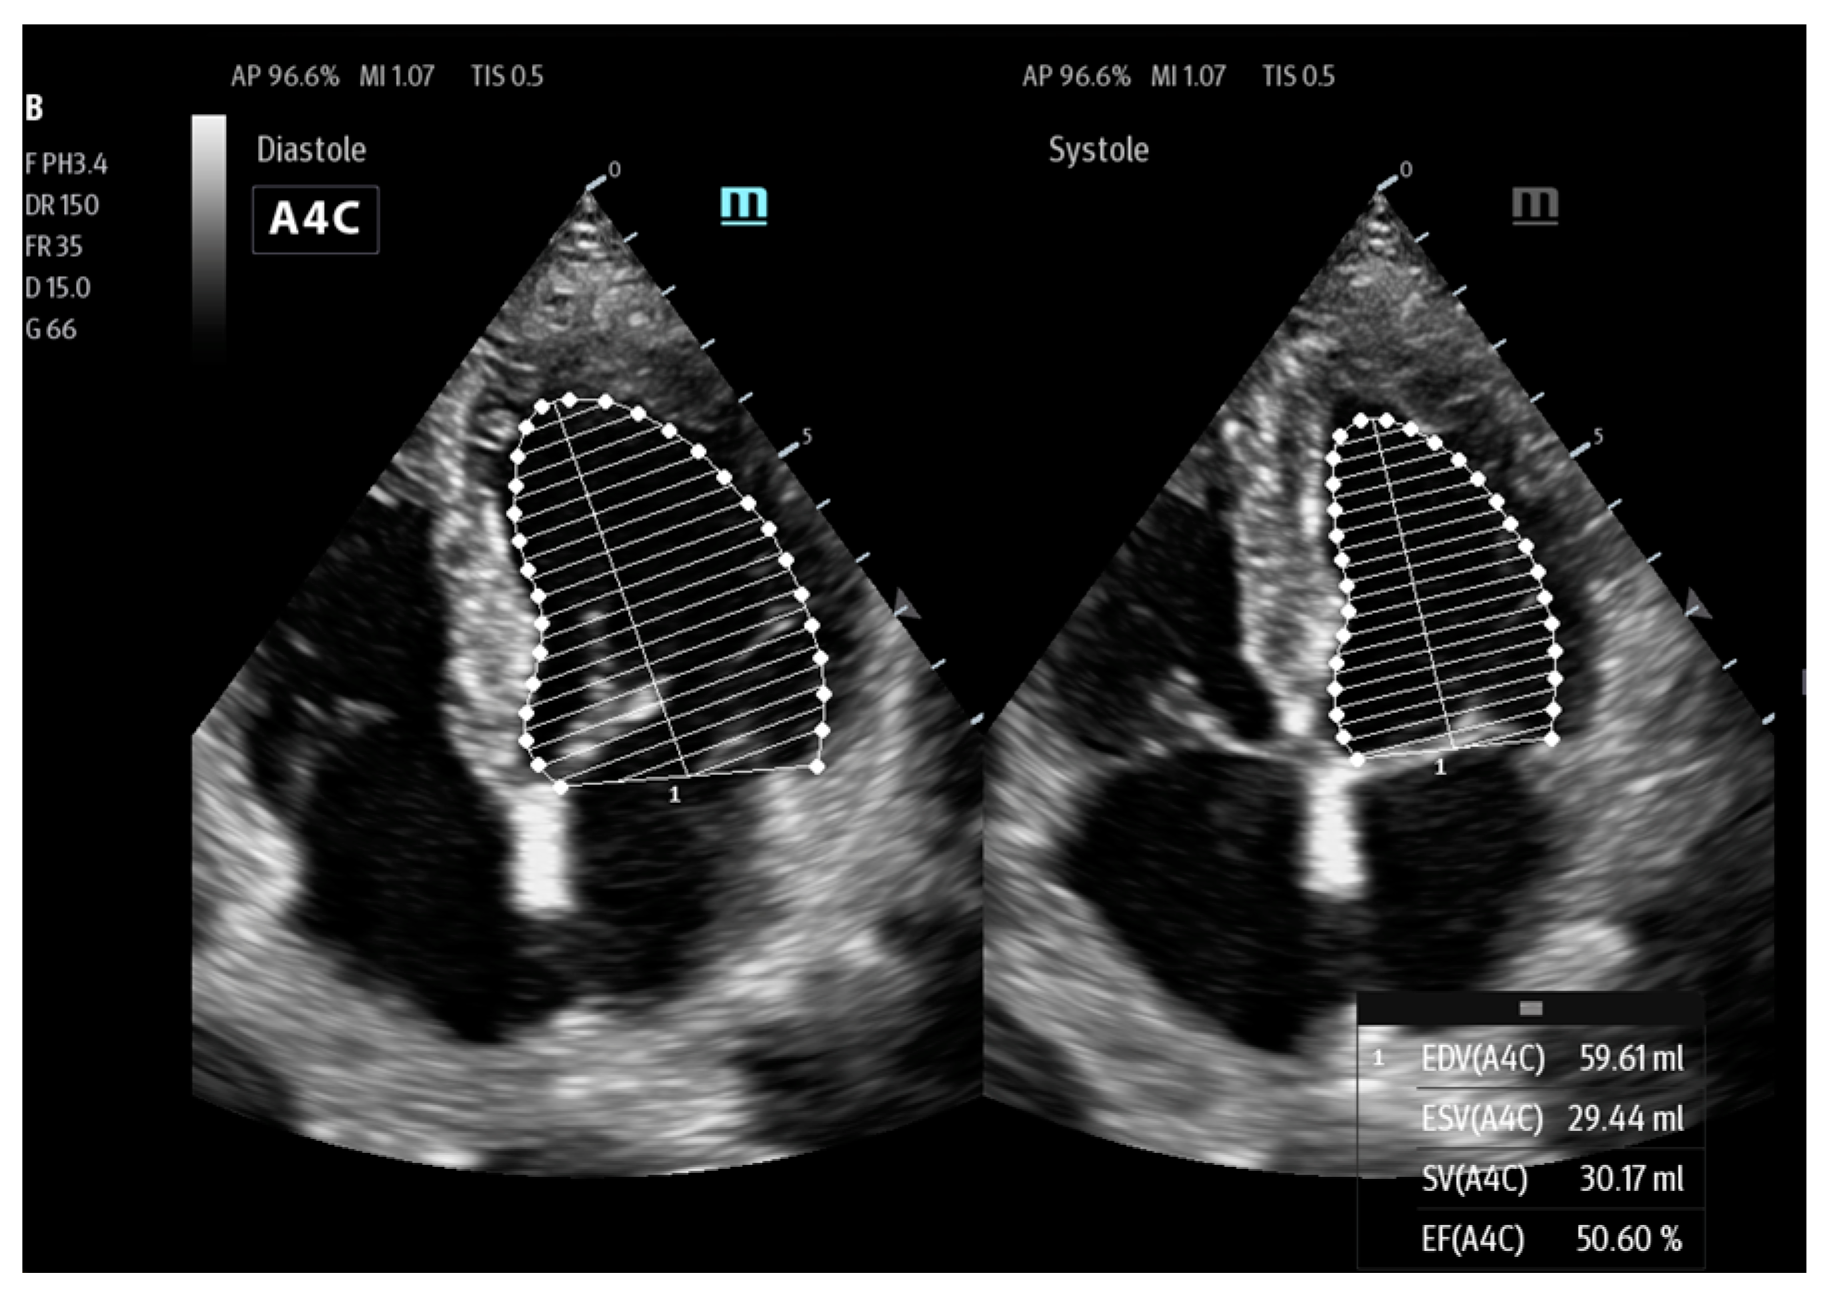

| AutoEF | Mindray | calculation of ejection fraction (EF) | Ultrasonographic assessment of cardiac function |

| LvivoEF | Philips | ||